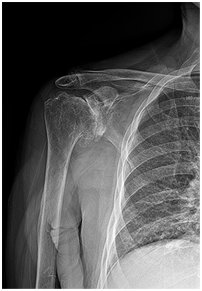

방치할 경우 발생 가능한 합병증

진행된 어깨관절염